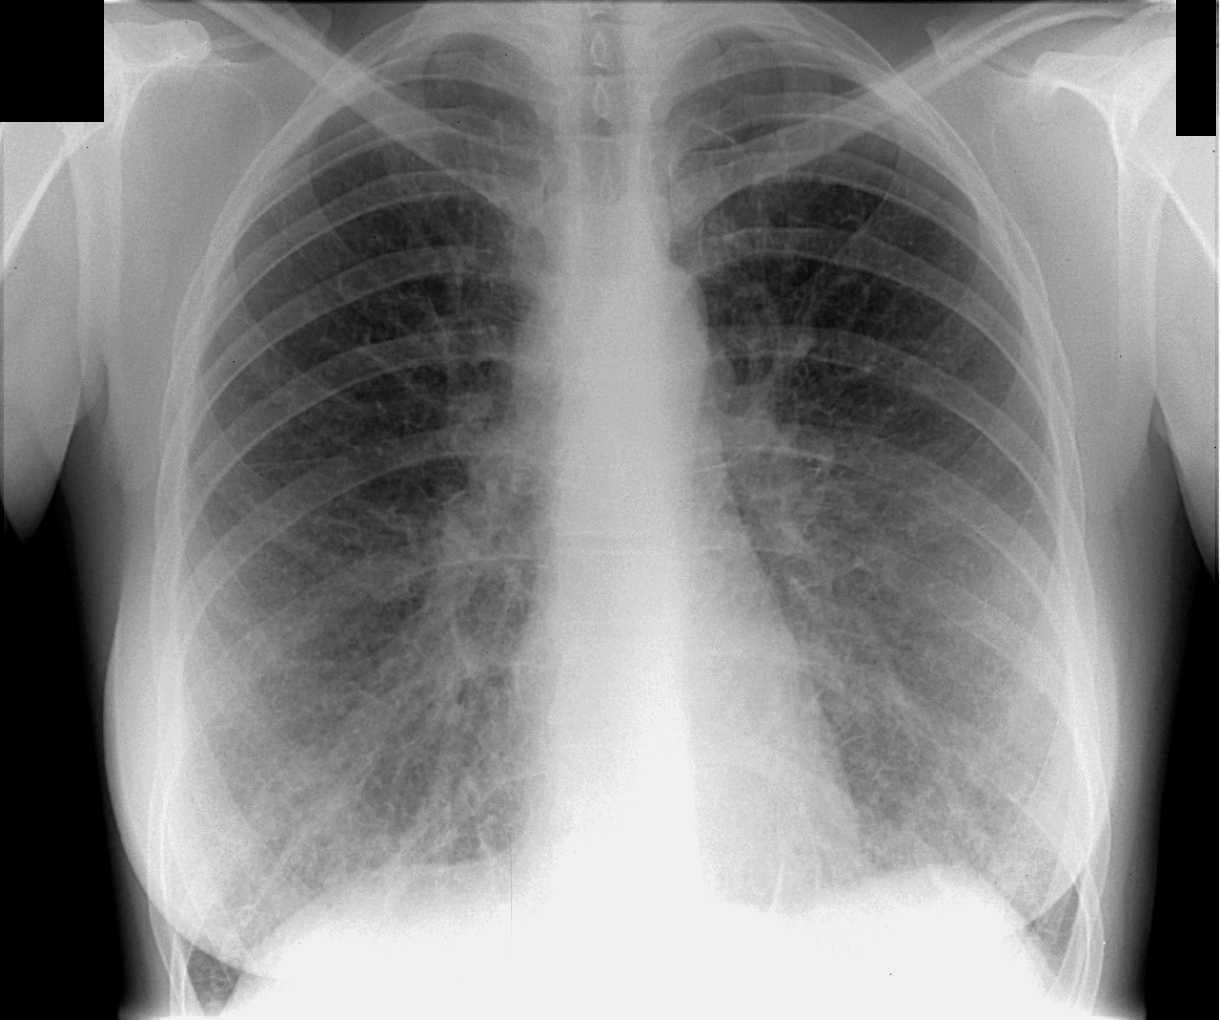

Рентген здоровых легких: примеры снимков и советы